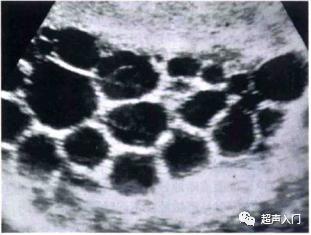

2、多囊型

表现为大的囊肿内有多个大小不等圆形小囊,呈葡萄状或蜂窝状,形成特征性 “囊中囊”征象。

多子囊型(CE2)

图源:人卫出版社教材及课件